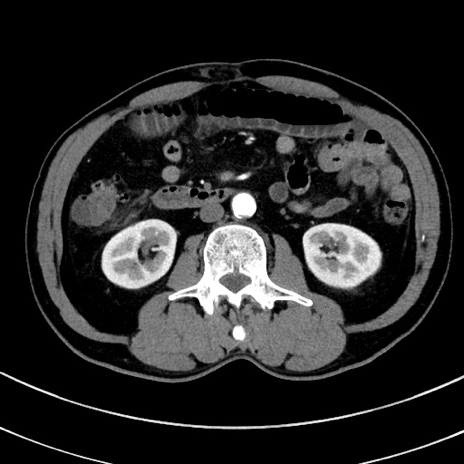

冠状断像

【症例】 60歳代男性

【主訴】 黒色吐物

【現病歴】 4日前から嘔気自覚、2日前の朝食後にも嘔気あり、自分で手で嘔吐反射起こし嘔吐したところ血が混ざっていたため受診。

【既往歴】 5年前汎発性腹膜炎を伴う急性虫垂炎で手術、高血圧、前立腺肥大症、高脂血症

【身体所見】 腹部正中に手術癩痕あり 腹部平坦・軟圧痛なし膨満感あり

【データ】WBC 8400、CRP 4.54